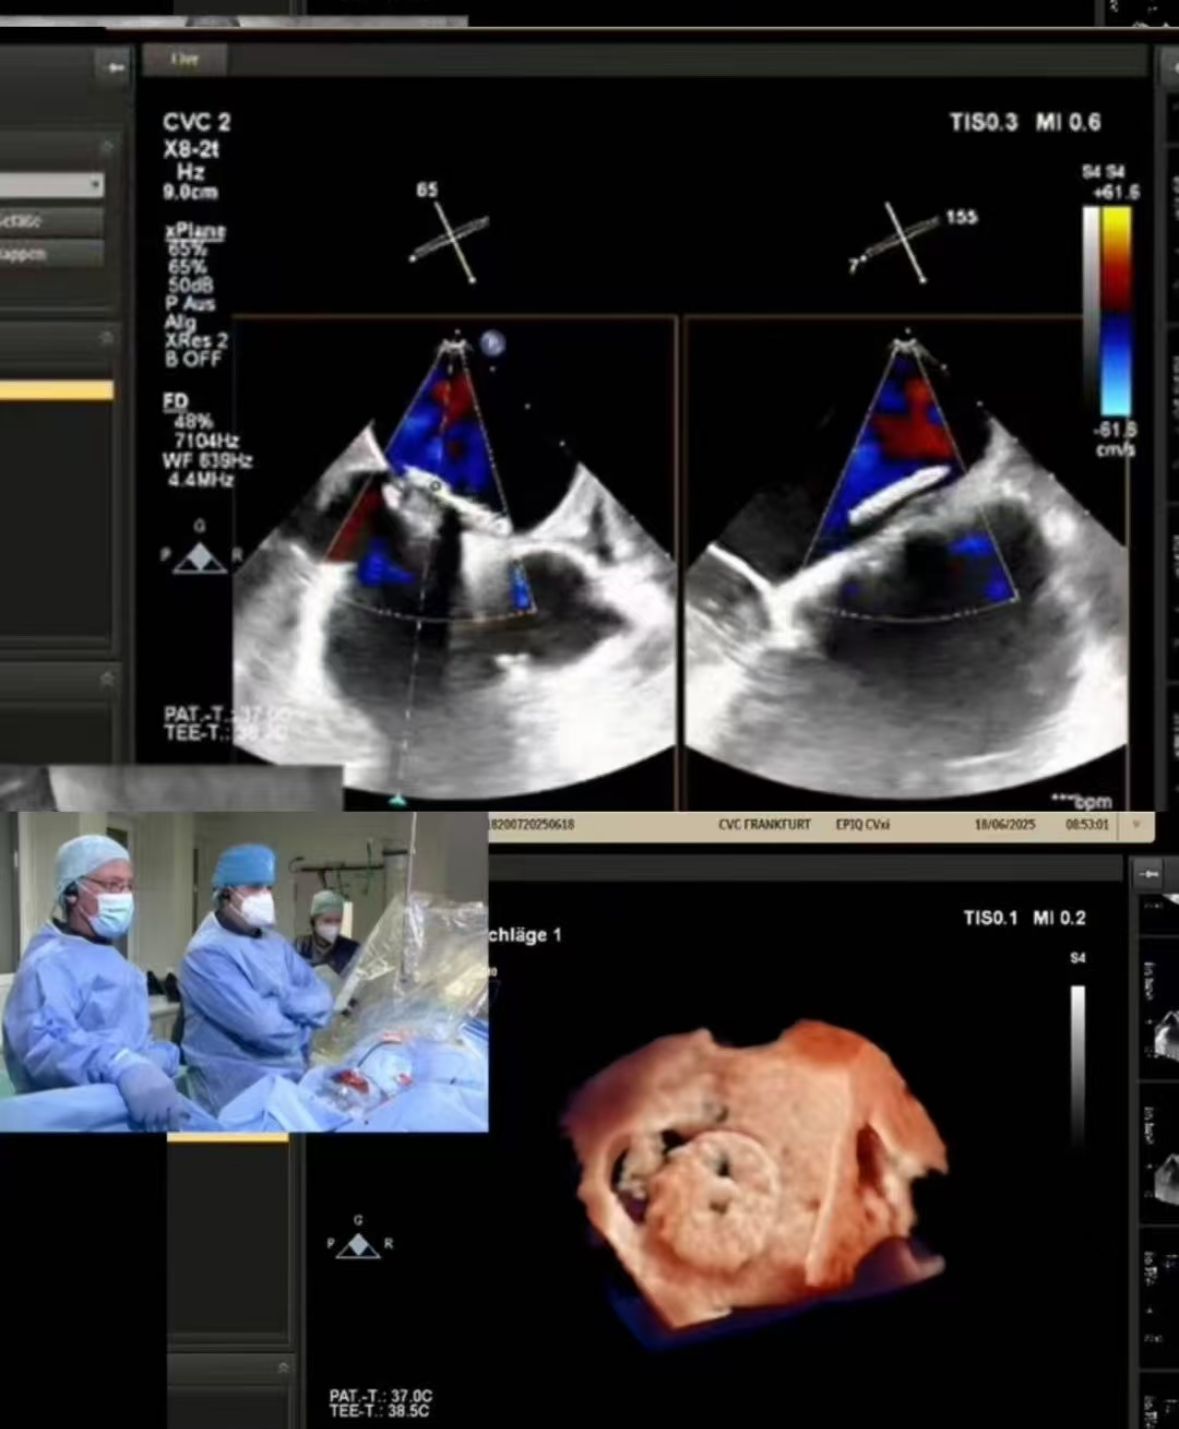

Thrilled to showcase our MemoSorb PFO Occluder – the world's first absorbable device (degrades to water & CO₂ within 1 year) – during a live broadcast from the Blue Room at CSI Frankfurt!

We streamed a complex PFO closure performed at CVC Frankfurt on a 60-year-old female patient with:

2. Precise closure: Real-time imaging guided perfect deployment in challenging anatomy (PFO tunnel fenestration).